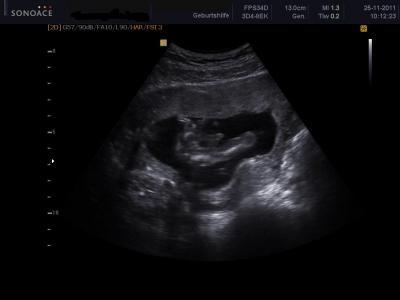

Hallo Ihr Lieben, ich war ja am Freitag spontan beim Arzt da ich Krämpfe im Bauch hatte. Es ist aber alles gut ! Baby geht es super :-) bin so happy. So nun zur Frage. Wenn Ihr euch das Bild anschaut, denkt Ihr auch es ist ein Junge ? Der Arzt konnte es mir nicht zu 100 % sagen aber er ist sich schon sicher wobei er auch sagte es kann sich noch ändern. Ich sehe ja das was zwischen den Beinchen baumelt aber ich finde es ist so groß , kann es auch die Nabelschnur sein oder so ? Rechts das Beinchen und daneben der "Schniedel" :-) Danke schon mal für die Antworten ! Lieber Gruß Lija

Hey :) Hab mir das Bild mal angesehn hmmm Hmm ich glaub es ist noch zu früh etwas zu sagen, sieht aber nach nem jungen aus :)

ne nix zu früh, dass ist ein Junge und das EINDEUTIG Die Hoden sind auch noch kurz nach dr Geburt so "prall",du kannst dich auf das Outing definitiv verlassen